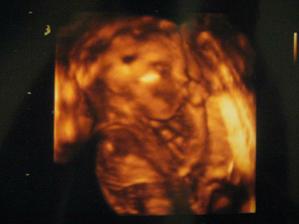

2. 3. 2011 Dneska jsme se byli vyfotit ve 3D 🙂 Chtěli jsme i video ale Kačenka měla půlnoc tak nebylo co točit 🙂